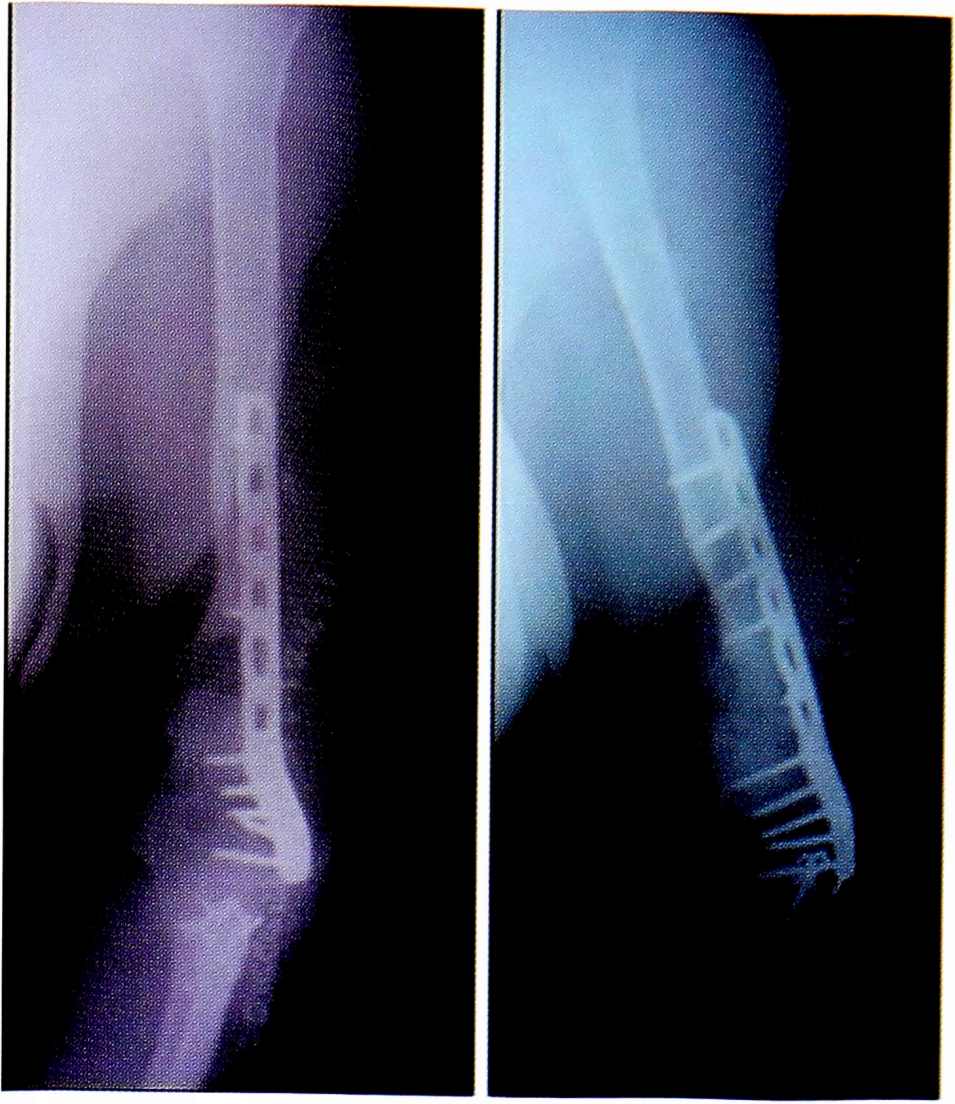

Консолидация перелома при кровоснабжаемой костной пластике была достигнута в 36 (88%) случаях в течение 4-6 мес (рис. 2): в группе применения малоберцового трансплантата консолидация была достигнута в 33 случаях, в группе трансплантата из мыщелка бедренной кости — в 3 случаях.

Рис. 2. Результаты оперативного лечения с использованием кровоснабжаемой костной пластикой.

Fig. 2. The results of surgical treatment using blood-supplied bone grafting.

Рис. 5. Пациентка И. Этапное оперативное вмешательство. а — замещение дефекта плечевой кости цементным спейсером; б — транспозиция торакодорсального лоскута в область мягкотканного дефекта плеча; в — послеоперационная рентгенограмма.

Fig. 5. Patient Stage I. operative interferencetion. a — replacement of defect of the humerus bone cement spacer; b —transposition of the thoraco-dorsal loof scoot in the region magadanniro defect of the shoulder; inkoperativnaya radiograph.

Pиc. 7. Оперативное лечение пациентки И.: пластика левой плечевой кости свободным кровоснабжаемым трансплантатом из малоберцовой кости.

Fig. 7. Surgical treatment of patient I.: plastic left humerus free perfused transplantthat of the fibula.